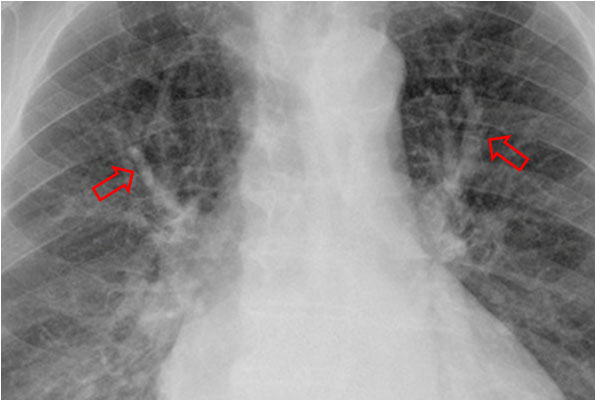

SIGNO DE LAS ASTAS DE CIERVO

Signo de hipertensión venosa pulmonar en la radiografía posteroanterior de tórax. Consiste en el engrosamiento de las venas de los campos pulmonares superiores (flechas) por redistribución del flujo, normalmente dirigido hacia las bases de forma preferente. Si la presión venosa pulmonar no se controla con este mecanismo fisiopatológico, se produce el edema intersticial y, finalmente, el edema alveolar.